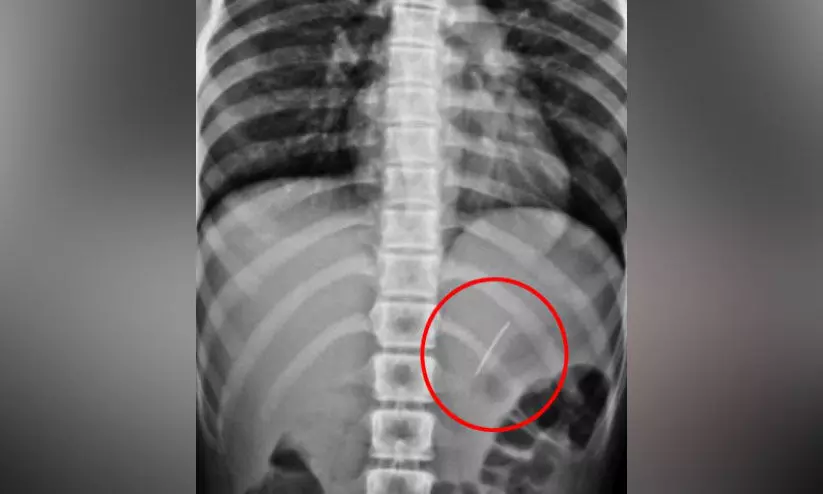

text_fieldsകുട്ടിയുടെ ആമാശയത്തിൽ കുടുങ്ങിയ പിൻ

സ്വകാര്യ ആശുപത്രിയില് പ്രവേശിപ്പിച്ചതിനെ തുടർന്ന്, തുടര് ചികത്സക്ക് പെരിന്തല്മണ്ണ കിംസ് അല്ശിഫയിലെത്തിച്ചു. എക്സ് റേ പരിശോധനയില് ആമാശയത്തില് പിന് തറച്ചതായി കണ്ടെത്തി.